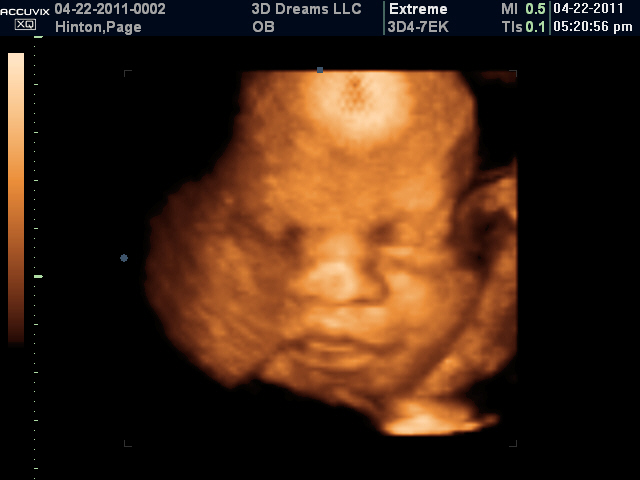

3D/4D Ultrasound

Chad and I have been anticipating seeing our "baby girl" for quite some time.  Yesterday afternoon, we got a sneak peek of our little angel at 3D Dreams in Baxter Village in Fort Mill.  We highly recommend this place.  Most OB/GYN offices do 3D/4D ultrasounds, but I had heard such good things about 3D Dreams that we decided to go there.  Our ultrasound was not rushed, the sonographer took her time showing us a lot of "cool" things we were seeing on the ultrasound.  We now have so many pictures of our baby girl that we will hopefully be held over another 10 weeks or so.  Here are a few sneak peeks of Reagan.

Her first smile

Her little foot

Opening her mouth

Laughing

Curled up and sleeping like Mommy